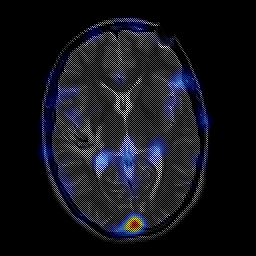

overlay -- Slice #14

[Home][Help][Clinical] Slice 14

Click on sagittal image to select slice. Click on thin tickmark to change timepoint, or thick tickmark for overlay.